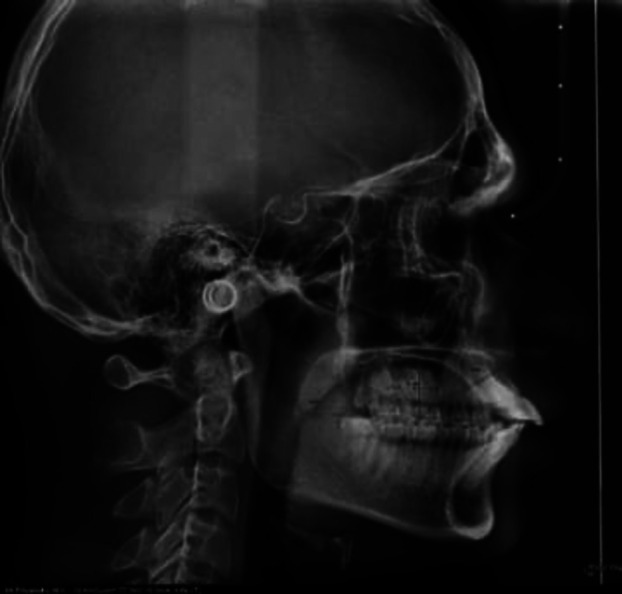

Material and methods: This retrospective study was conducted in the Department of Orthodontics and Dentofacial Orthopedics, Manipal College of Dental Sciences, Mangalore. The records of 126 subjects including skeletal class I subjects as the control group (n = 63) and skeletal class III patients as the experimental group (n = 63) were obtained. The tongue-to-palate distance of all the subjects was measured using the method described by Graber (Graber et al., 1997) on lateral cephalograms. CBCT images were standardized and acquired by keeping the patient's head in the natural position. Buccolingual inclinations were measured on CBCT coronal sections as the angle between the reference plane (line perpendicular to the line joining the buccal and lingual crest of the alveolar bone) and the long axis of each tooth. SPSS software, version 25.0 was used to perform the statistical analyses. To analyze the association between tongue posture and buccolingual inclination of teeth, the Pearson correlation coefficient was calculated, with a power of 80%.